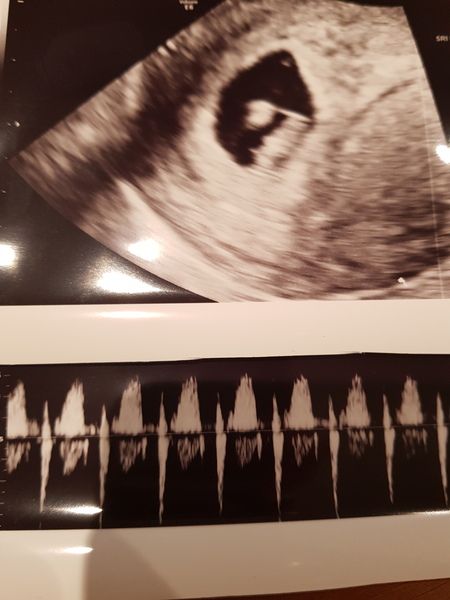

I'm 10 weeks today and had a scan at 7+2, the sonographer was very happy with the heartbeat and kept saying it was beautiful. I could see it and then she also let me hear it which was unbelievable!

I'll attach a picture of my scan even if it was almost 3 weeks ago! It also shows the heartbeat which is pretty cool. Hoping it will be much bigger on Thursday!

Curlywurly3 · 24/11/2018 06:06

Oops forgot to add the photo x